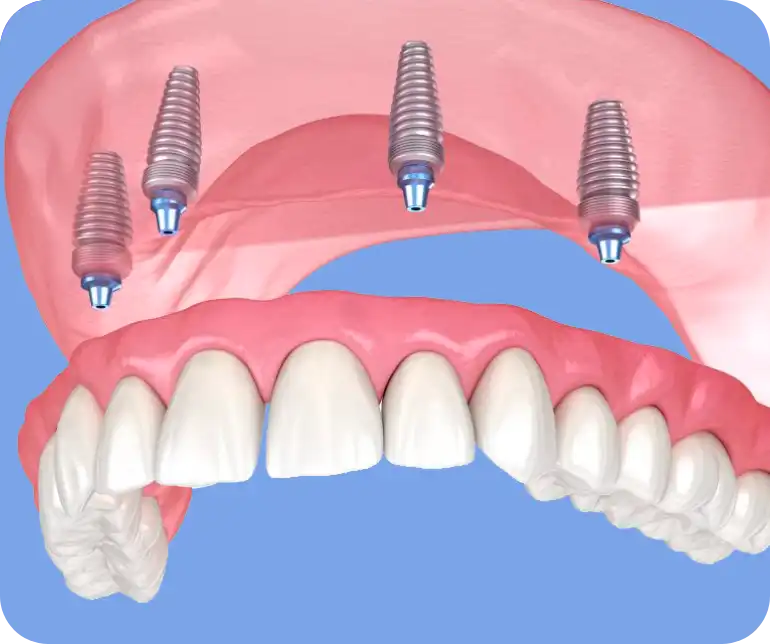

Hai perso i denti? Scopri gli impianti dentali e la chirurgia

Ritrova la funzionalità e l’estetica del tuo sorriso.

Offriamo soluzioni protesiche fisse e mobili personalizzate, utilizzando materiali all’avanguardia per restituire bellezza e funzionalità al tuo sorriso.

Dalle capsule metal-free alle protesi mobili esteticamente impeccabili, il nostro team combina arte dentale e tecnologia per trasformare il tuo sorriso e migliorare la tua qualità di vita.